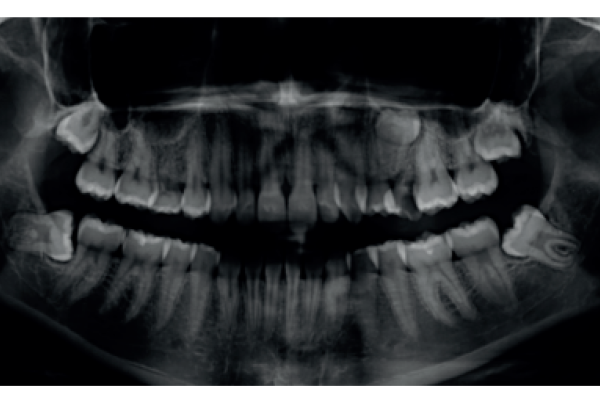

Prevención de defectos periodontales tras la exodoncia de terceros molares inferiores con injerto de dentina autógena: evaluación a 6 meses de un caso clínico